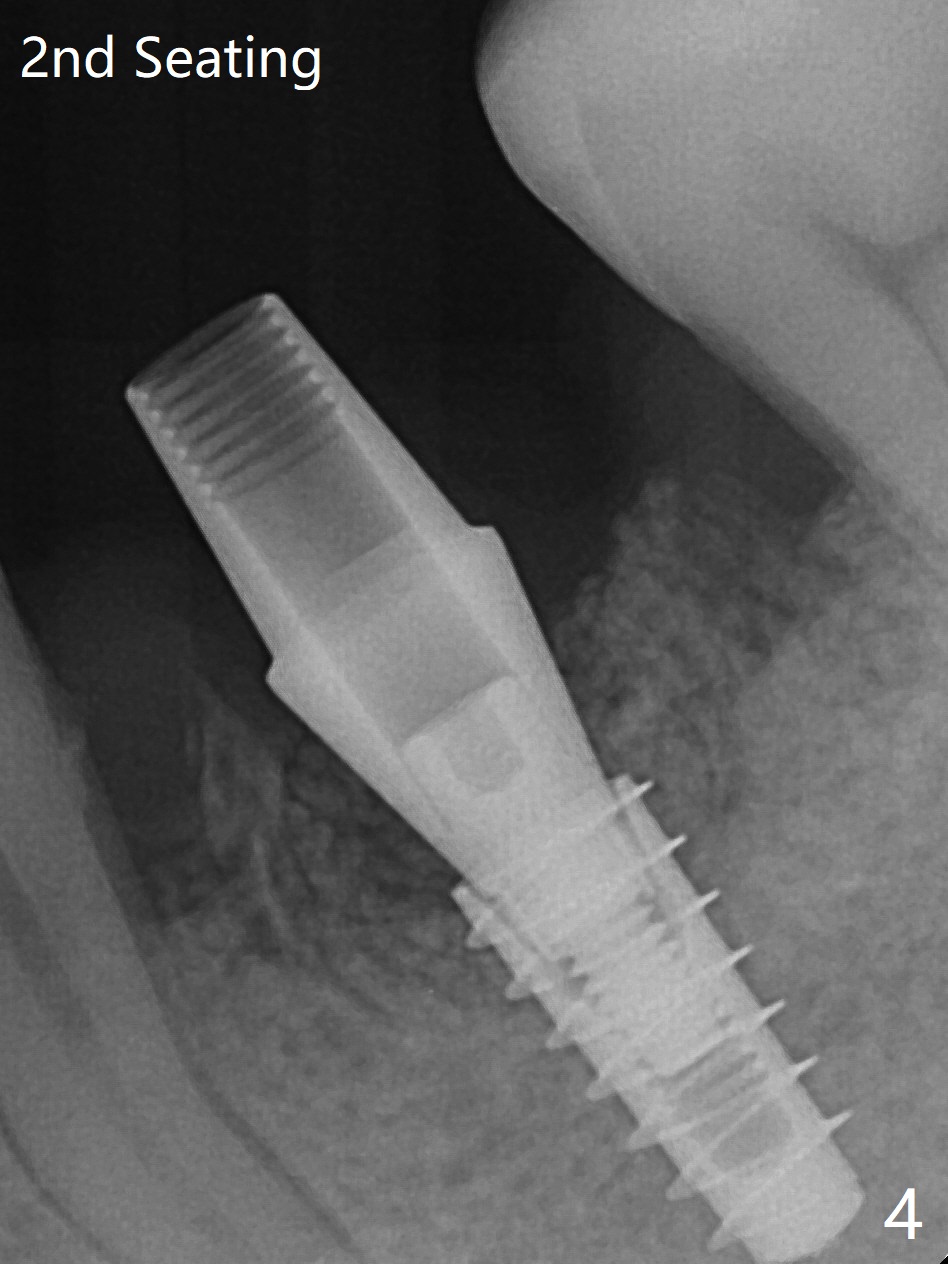

In spite of smoking reduction (1ppwk), the infection at #19, including buccal fistula (Fig.1 <) seems to be so severe that it affects pain threshold. Local anesthetics have to be added, including Bupivacaine IANB. When 4x10 mm drill is being applied, the patient feels pain. The plan is to use 4x11.5 mm drill as a final one. A 4x9 mm dummy implant is placed with 2.8 mm implant exposed (Fig.2 >), but it is subcrestal mesiodistally. Primary stability of a definitive 4.5x9 mm implant is satisfactory (Fig.3), but after initial bone graft, a 5x5.7(4) mm abutment is unable to be seated completely (<). Following 4.6 and 5.6 mm bone profile drills, the abutment remains incompletely seated (Fig.4). After fine turning, the abutment is fully seated; final round of bone graft (sticky bone) is placed mesiodistally (Fig.5 *) and buccolingually (Fig.6,7). It appears that there is tight fit between IBS implant and abutment. It is hoped that the excess bone graft with PRF is able to cover the coronal portion of the implant. If not, socket preservation should be done in this situation. In fact the implant is not placed lingual enough as compared to the design (Fig.6'). A 4.5 mm cortical drill should be used in a crown down fashion. In fact there is bone coverage coronally 5 months postop (Fig.8). Return to Prevent Molar Periimplantitis (Protocols, Table) No Deviation 12/14 Xin Wei, DDS, PhD, MS 1st edition 02/11/2020, last revision 06/30/2020